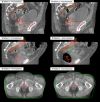

Methods: Pre-treatment cone beam computed tomography (CBCT) scans were acquired daily and post-treatment CBCTs for the first week then weekly on 46 patients. The displacement between the scans was calculated retrospectively to measure IFD of the prostate bed (PB). The marginal miss (MM) rate, and the effect of time between imaging was assessed.

Results: A total of 392 post-treatment CBCT's were reviewed from 46 patients. The absolute mean (95% CI) IFD was 1.5 mm (1.3-1.7 mm) in the AP direction, 1.0 mm (0.9-1.2 mm) SI, 0.8 mm (0.7-0.9 mm) LR, and 2.4 mm (2.2-2.5 mm) 3D displacement. IFD ≥ ± 3 mm and ≥ ± 5 mm was 24.7% and 5.4% respectively. MM of the PB was detected in 33 of 392 post-treatment CBCT (8.4%) and lymph nodes in 6 of 211 post-treatment CBCT images (2.8%). Causes of MM due to IFD included changes in the bladder (87.9%), rectum (66.7%) and buttock muscles (6%). A time ≥ 9 min between the pre and post-treatment CBCT demonstrated that movement ≥ 3 mm and 5 mm increased from 19.2 to 40.5% and 5 to 8.1% respectively.

Conclusions: IFD during PB irradiation was typically small, but was a major contributor to an 8.4% MM rate when using daily soft tissue match and tight anisotropic margins.